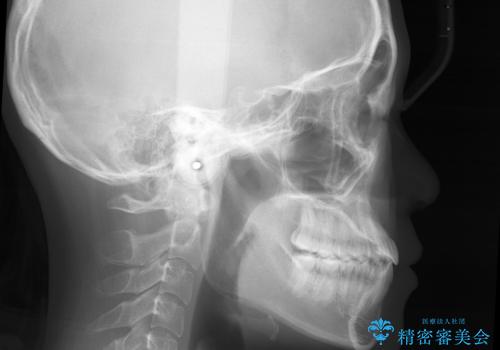

こちらの患者様の場合、上の前歯のガタつきが原因で口を閉じる際に上下の前歯の先端同士が先に当たってしまい、そこからさらに深く噛み込もうとすると下顎が前にずれていってしまうという、機能性の反対咬合であることが検査の結果わかりました。

その原因は ①骨格的問題 ②機能的問題 の2つに大きく分かれます。

①に関しては外科的手術を併用した矯正治療を必要とする場合が多く、大学病院や専門の設備を備えた医院での治療が必要となります。

原因が②であった場合は、手術を必要とせず口腔内ではの位置を変えてあげるだけで噛み合わせや顔貌を変化させることができる場合があります。